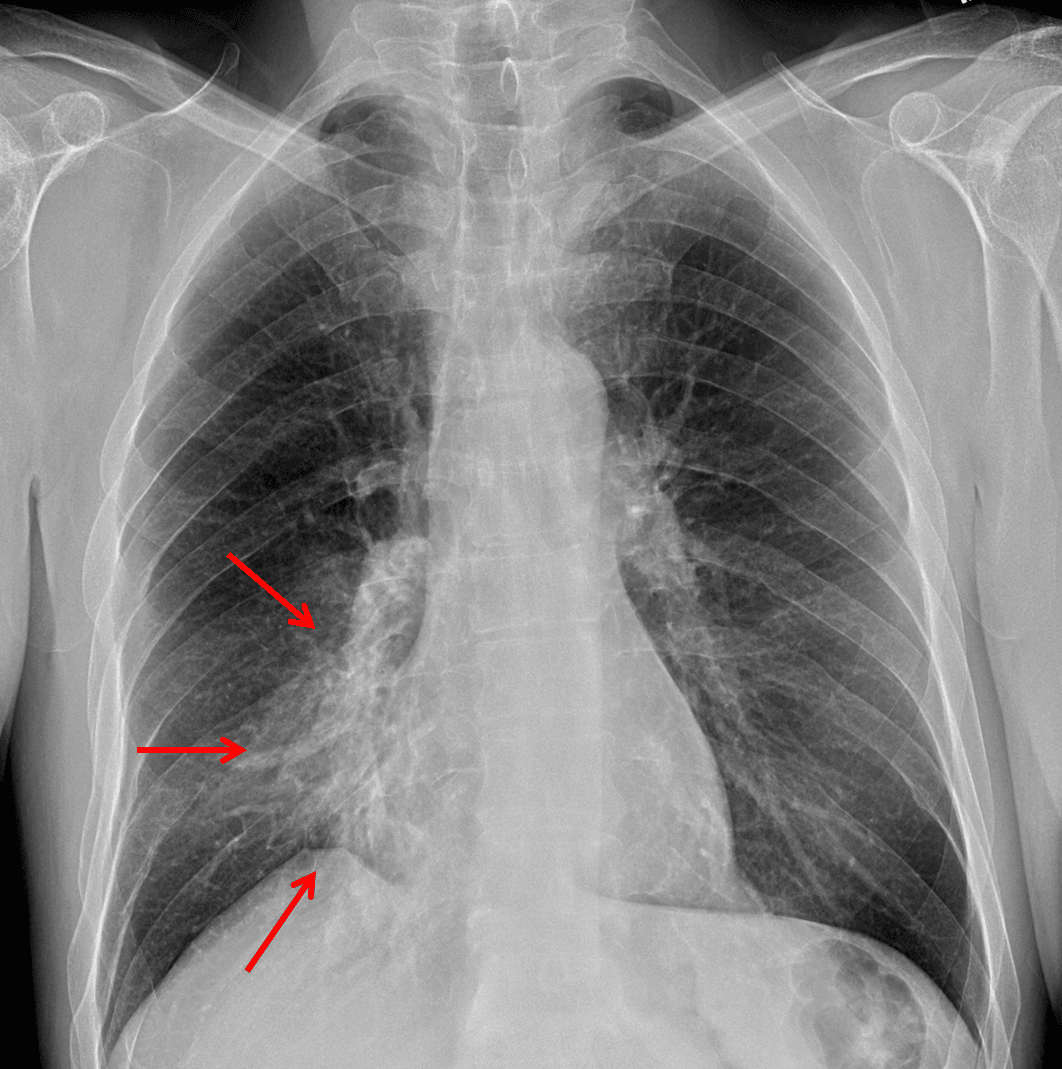

Red arrows: hazy airspace opacity with obscuring of the right heart border.